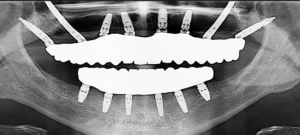

Managing Implant Overload and Bruxism: Strategic Implant Protocols to Protect Your Fixed Teeth

Implant overload and bruxism remain two of the most common – but often underestimated – reasons why dental implants fail.

Dental implants have transformed modern dentistry by providing patients with a permanent and functional replacement for missing teeth. However, not all